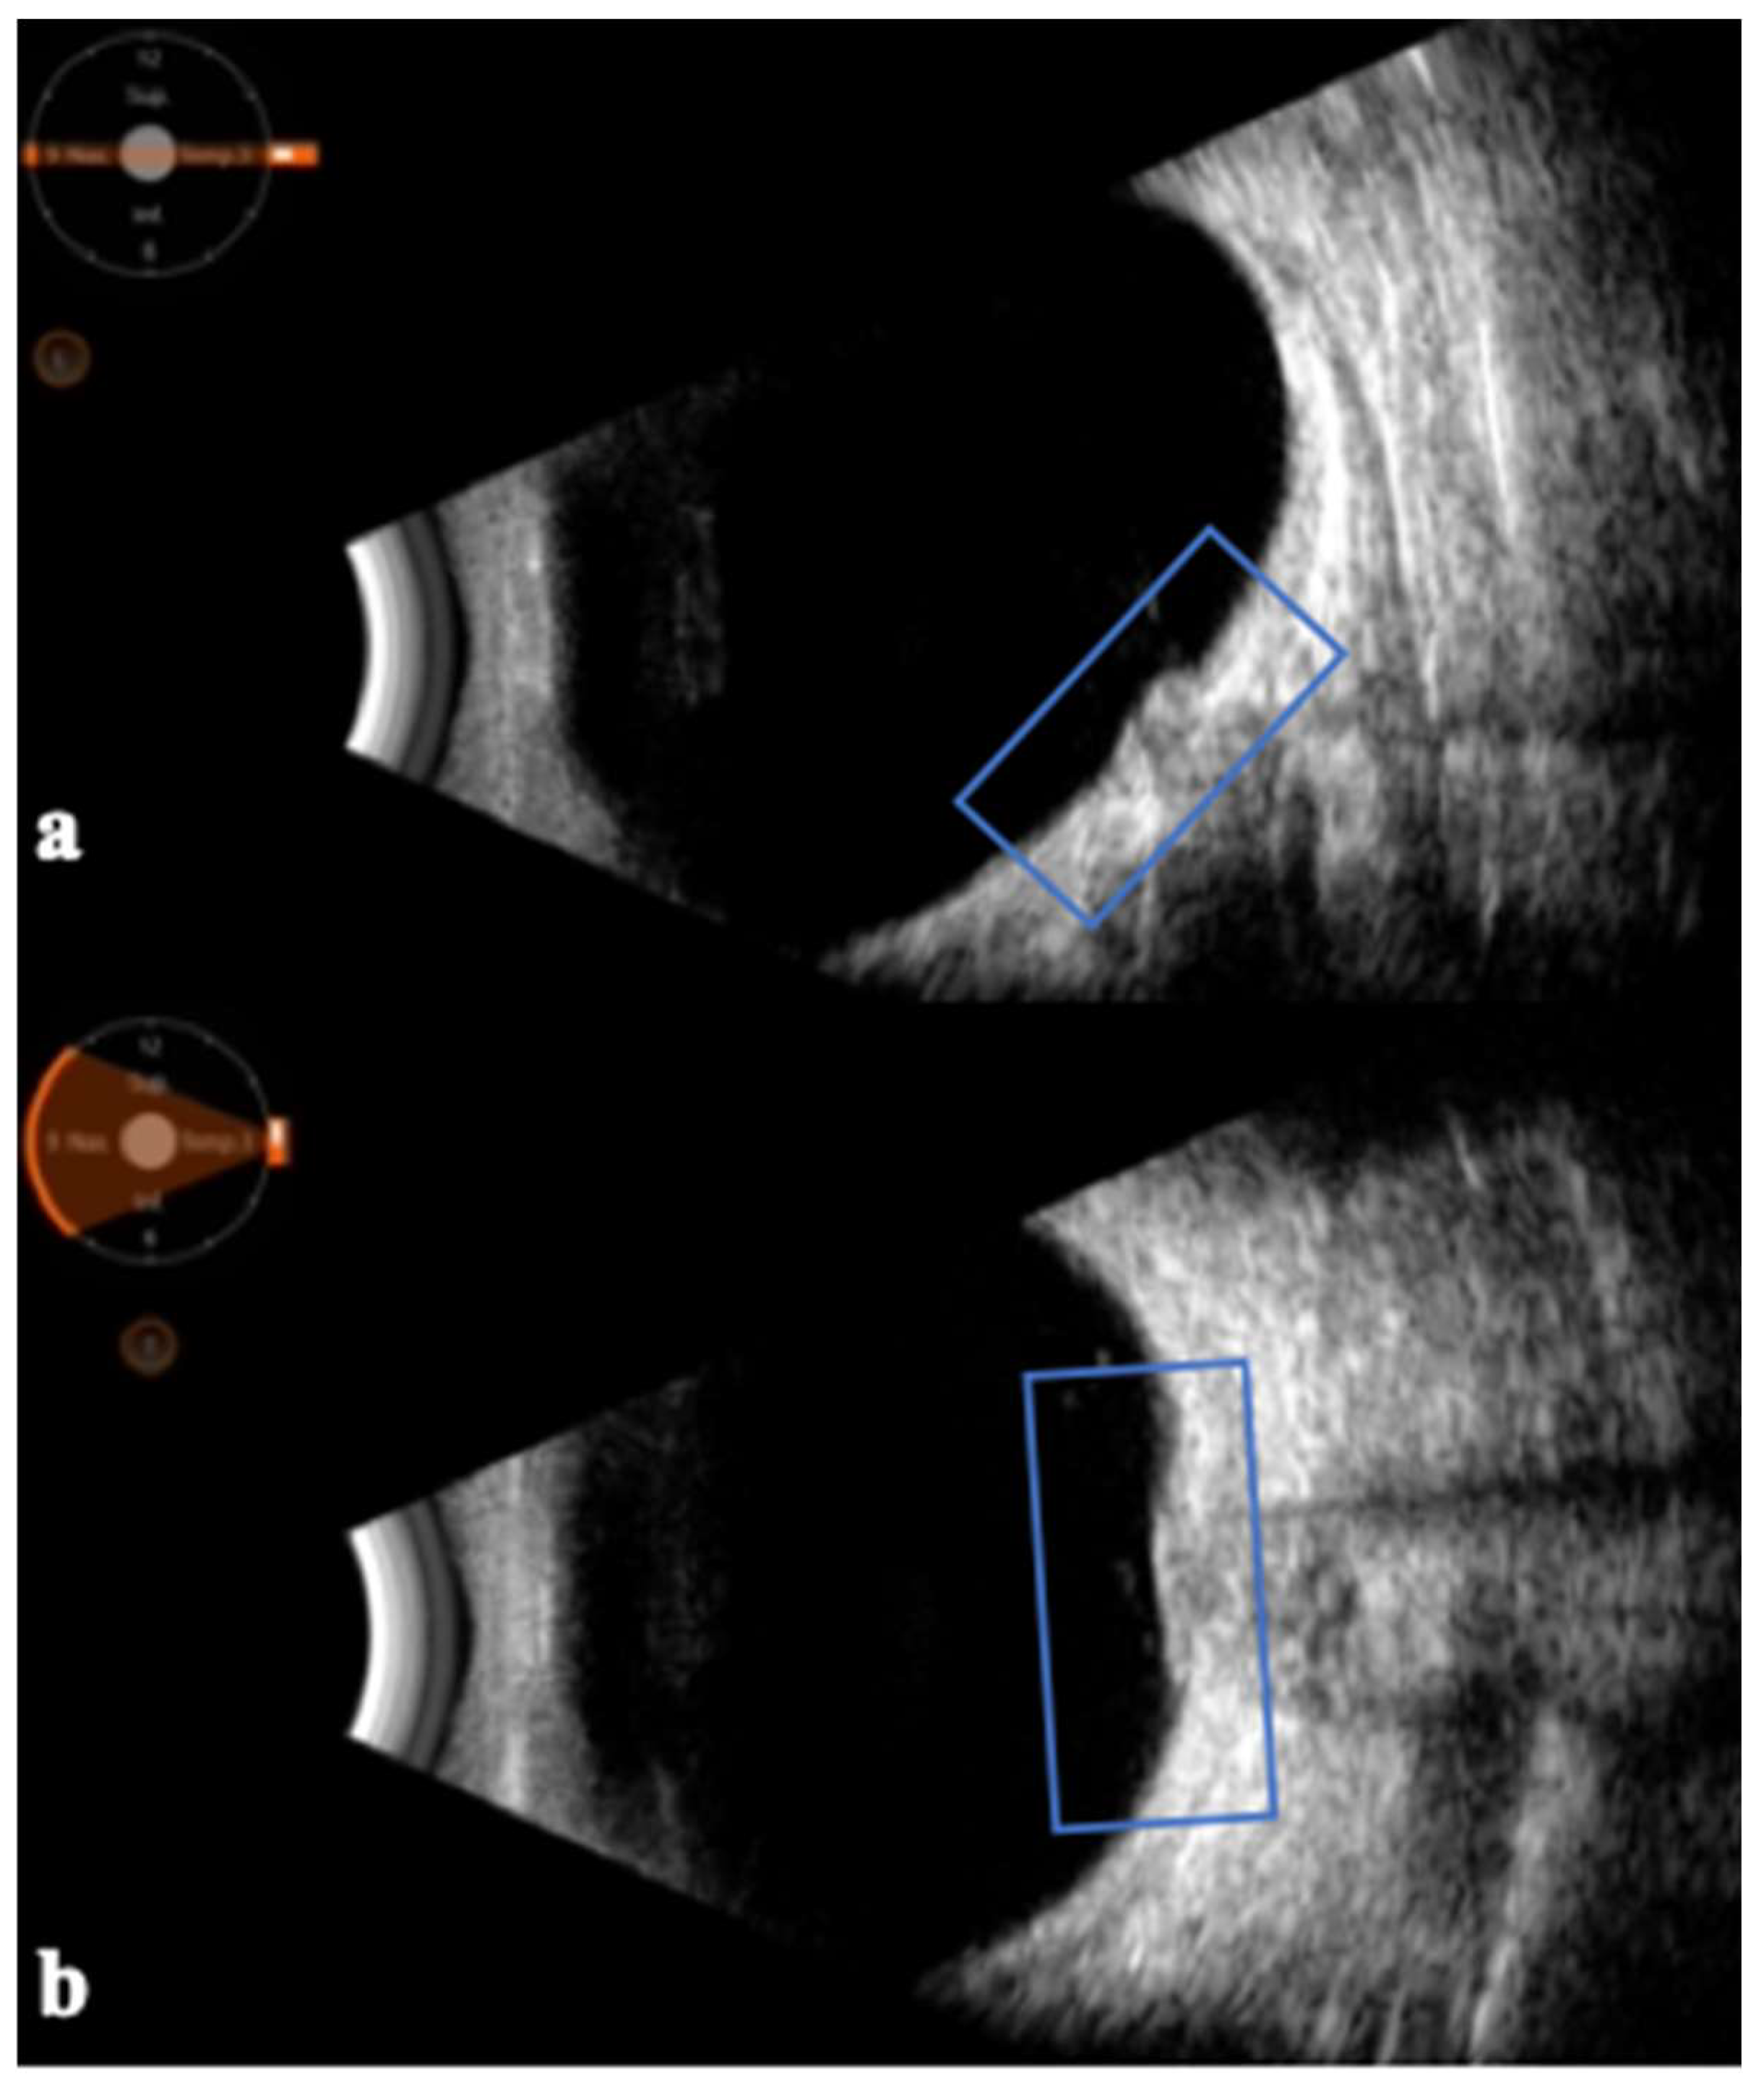

- Lochner, P.; Cantello, R.; Brigo, F.; Coppo, L.; Nardone, R.; Tezzon, F.; Raymkulova, O.; Strigaro, G.; Comi, C.; Leone, M.A. Transorbital sonography in acute optic neuritis: A case-control study. AJNR Am. J. Neuroradiol. 2014, 35, 2371–2375. [Google Scholar] [CrossRef] [PubMed]

- Lochner, P.; Leone, M.A.; Fassbender, K.; Cantello, R.; Coppo, L.; Nardone, R.; Zorzi, G.; Lesmeister, M.; Comi, C.; Brigo, F. Transorbital Sonography and Visual Outcome for the Diagnosis and Monitoring of Optic Neuritis. J. Neuroimaging 2017, 27, 92–96. [Google Scholar] [CrossRef]

- Kwon, Y.J.; Kim, Y.H.; Baek, S.H.; Son, M.H.; Lee, J.H.; Kim, B.J. Transorbital ultrasonography in acute optic neuritis: Can it be a supportive diagnostic tool? Mult. Scler. Relat. Disord. 2019, 31, 54–58. [Google Scholar] [CrossRef]

| Saigh et al. (2019) | [47] | 59-year-old female patient with progressive unilateral visual loss while she was receiving outpatient treatment for relapsing–remitting multiple sclerosis | B-scan ultrasonography | Transorbital ultrasound revealed a disparity between the optic nerve sheath diameters of the affected and nonaffected eyes and striking optic nerve edema in the affected eye, thus diagnosing an acute optic neuritis. |

| Kwon et al. (2019) | [48] | 17 patients with first-attack unilateral acute optic neuritis | B-scan ultrasonography | Ocular ultrasonography revealed thickening of the optic nerve diameter and optic nerve sheath diameter on the affected side compared with the unaffected side. |